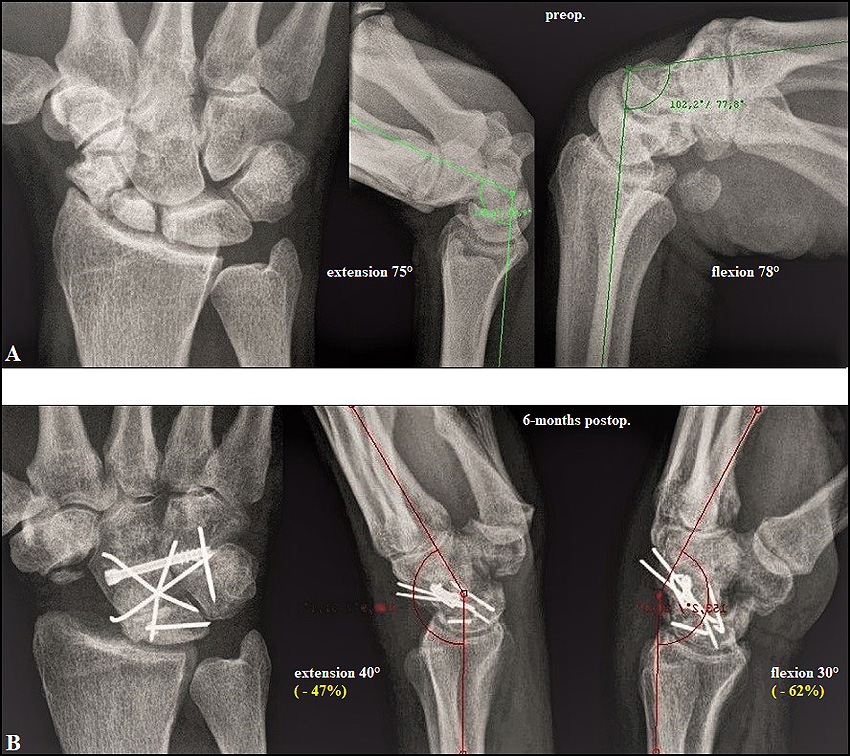

Four-corner fusion of the wrist: clinical and radiographic outcome of …

Four-corner fusion of the wrist: clinical and radiographic outcome of …

Relationship Between Wrist Motion and Capitolunate Reduction in Four …